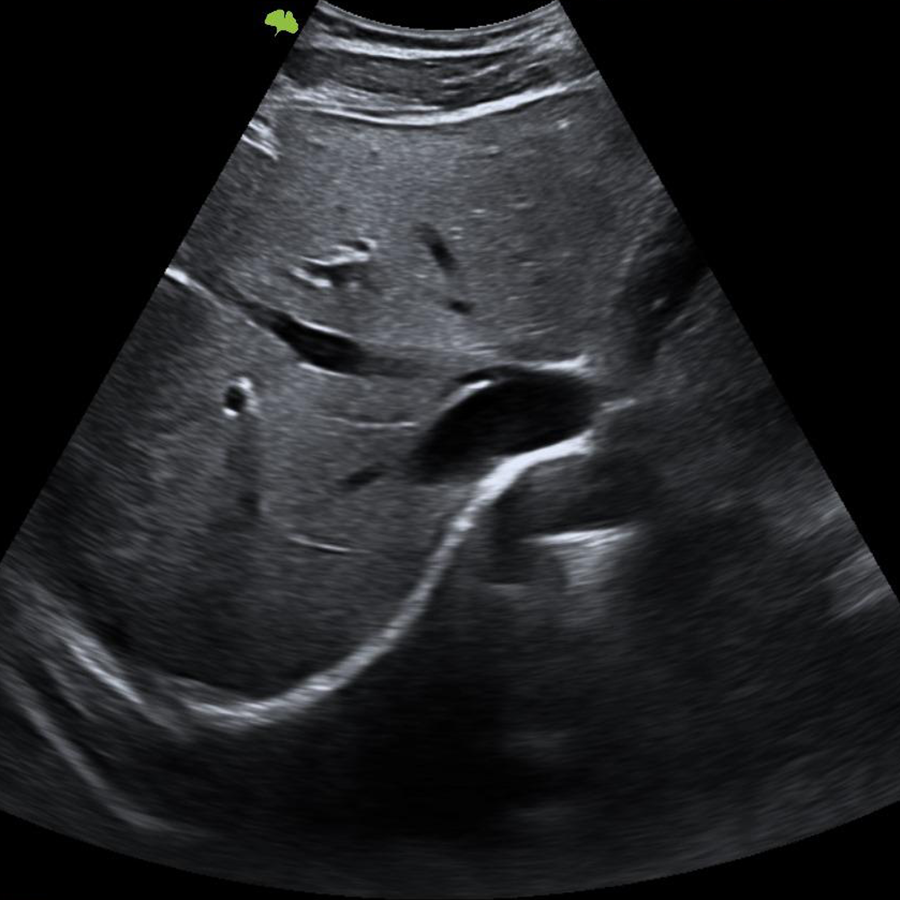

- Impulsado por la avanzada plataforma VLucid+, el nuevo VINNO S300 ofrece una solución en ecografía eficiente gracias a su interfaz intuitiva, diseñada alrededor de las necesidades y exigencias de la práctica clínica moderna, de esta forma conseguimos brindar una solución compacta para obtener imágenes de forma rápida y fluida en la práctica diaria.

Doppler

- Modo B